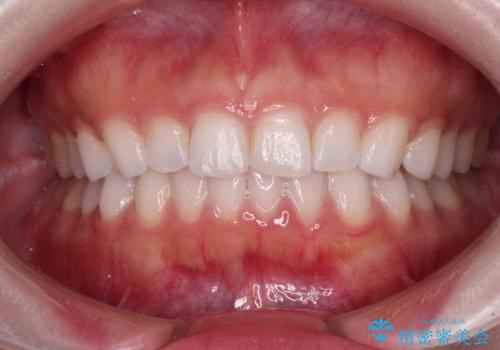

- 矯正治療で歯列を整えた後、前歯の形が気になった患者様です。

矯正前の歯列の影響で、前歯の先端が非対称にすり減ってしまったため、矯正治療後の形が非対称になっていました。

むし歯はなく、矯正治療で咬み合わせが改善していたので、侵襲量の少ないラミネートベニアにて治療することとしました。

ラミネートベニアは切削量が少ないことがメリットとしてあげられますが、色調を周辺と合わせられないこと、接着境界線が長く汚れや歯石が溜まりやすいことがデメリットとして考えられます。

また、接着境界線にむし歯がある場合には適用外となるなど、適用症例を選ぶため、治療に際して担当医としっかりと相談することが大切です。